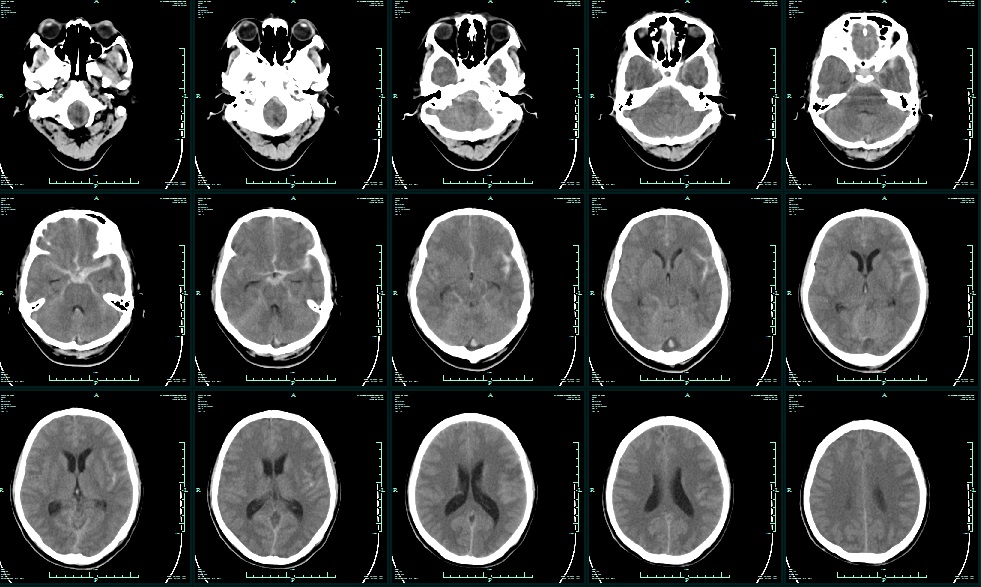

术前CT